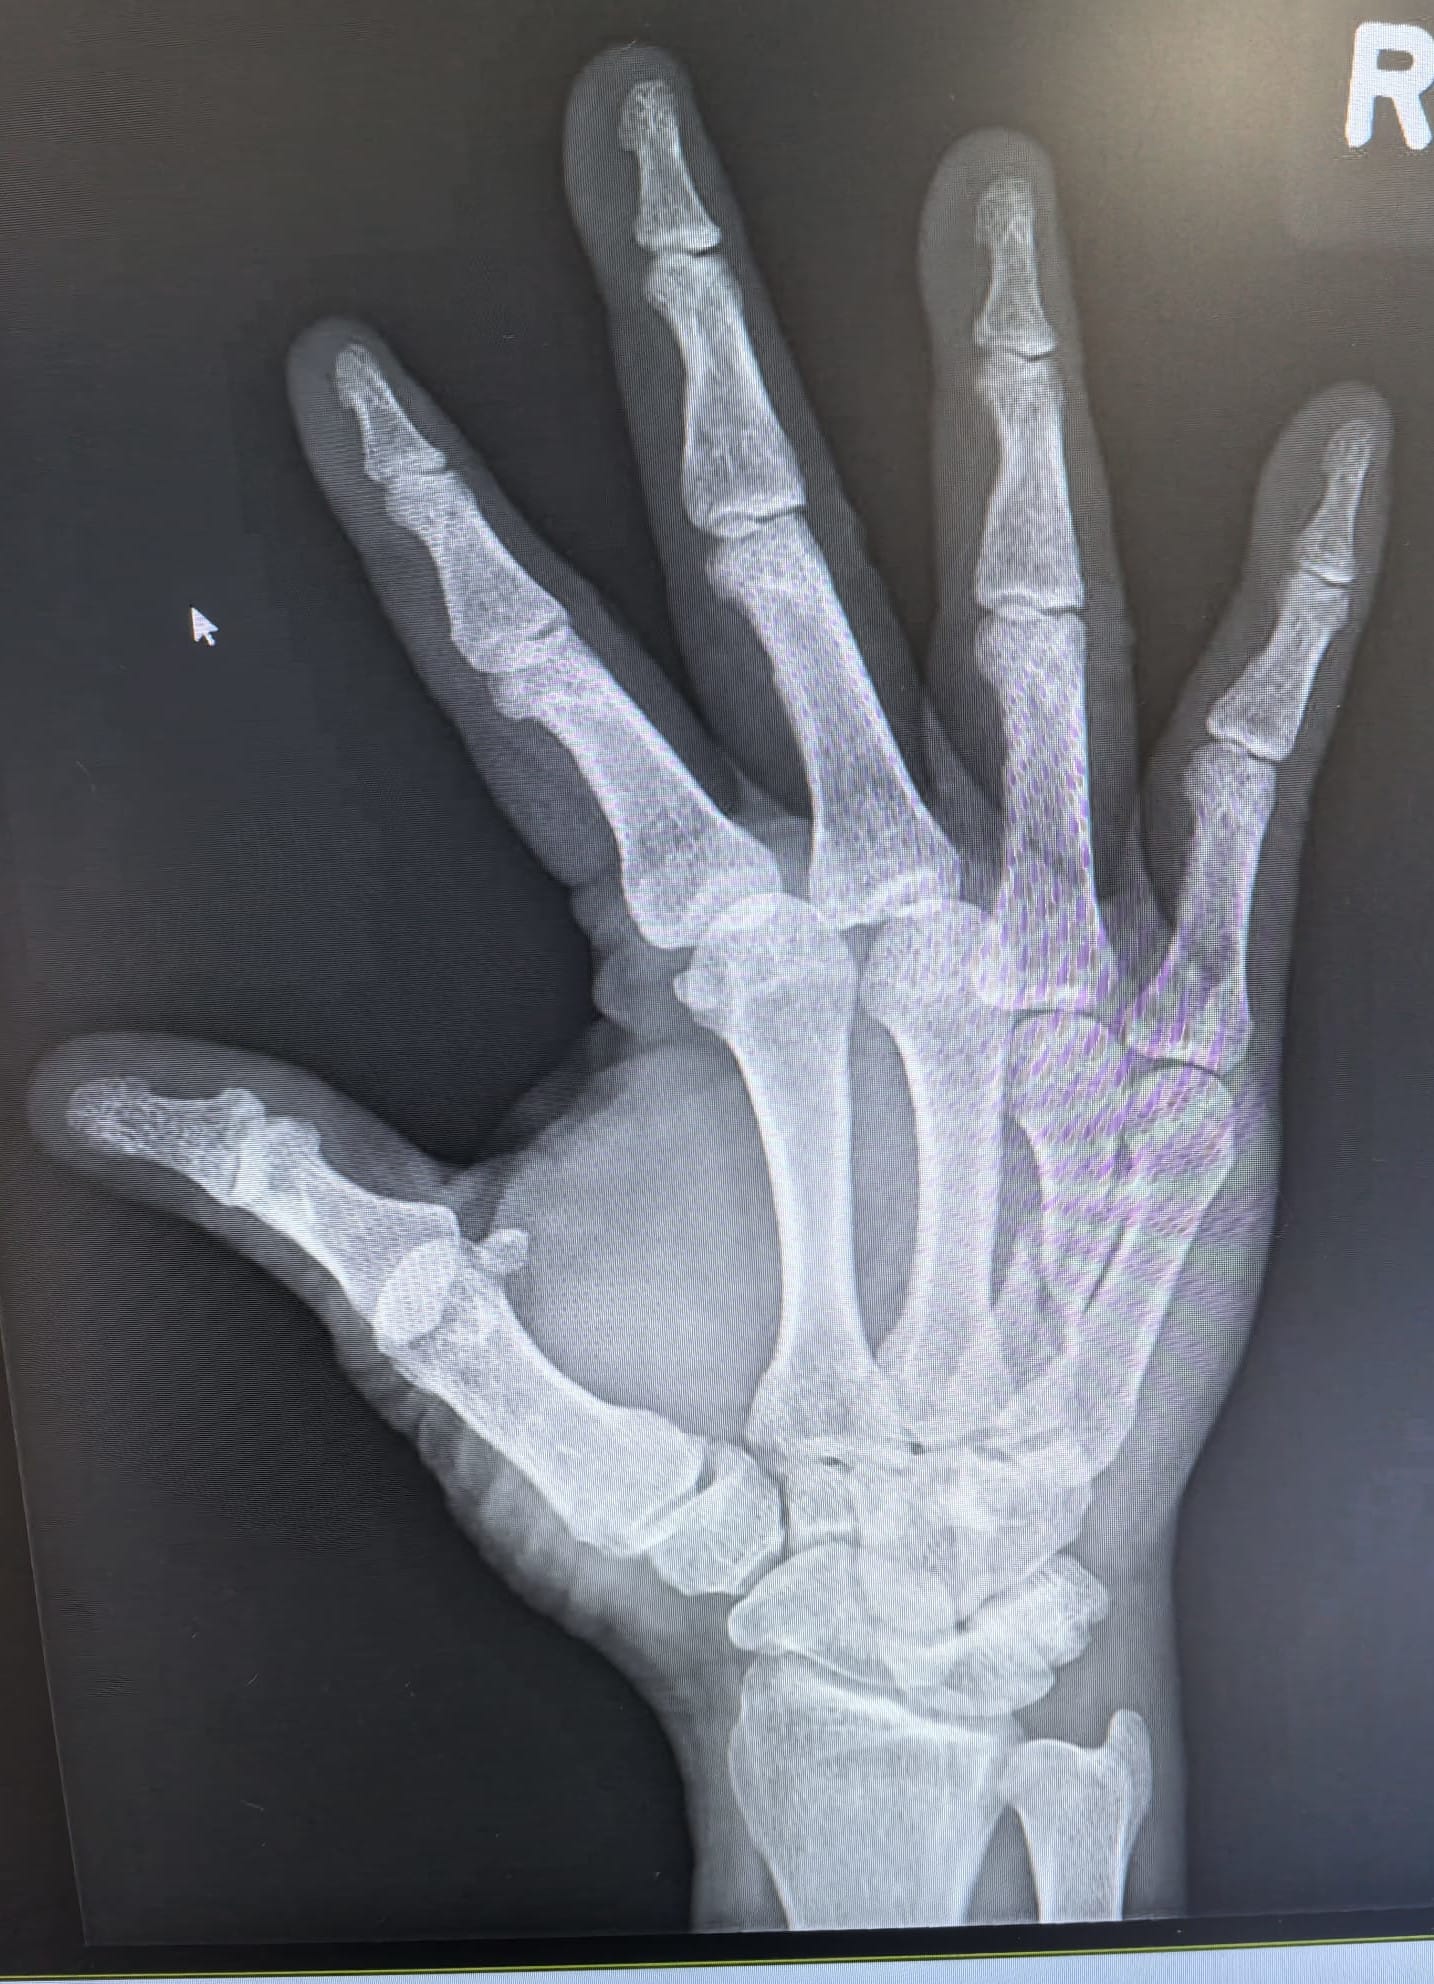

I fractured my right hand in April during a basketball game. Four months largely out of action, trying to run multiple companies one-handed. Literally.